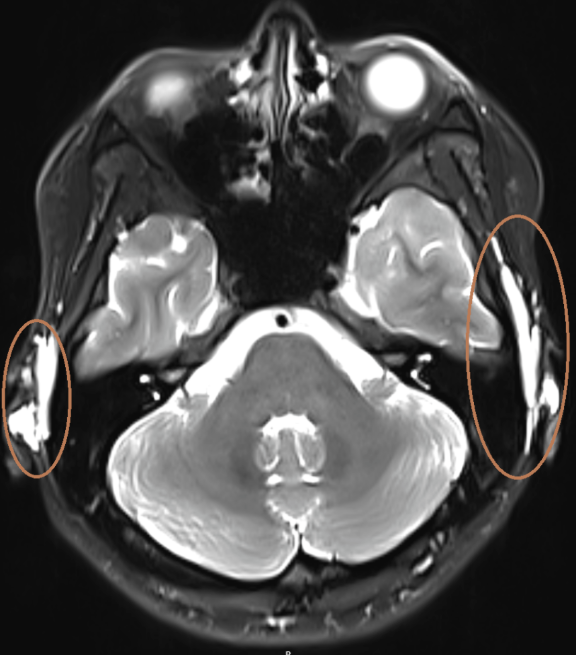

▲双侧耳后条片状T2压脂序列高信号填充物

她辗转多家医院,接受了透明质酸溶解酶注射、针灸、甲钴胺营养神经治疗…一个月过去,右脸依然毫无起色。针对她的面诊主诉,在北京中心做了MRI颌面部平扫+增强+神经成像,发现右侧面神经乳突段、腮腺段增粗、信号增高,考虑右侧面神经炎。